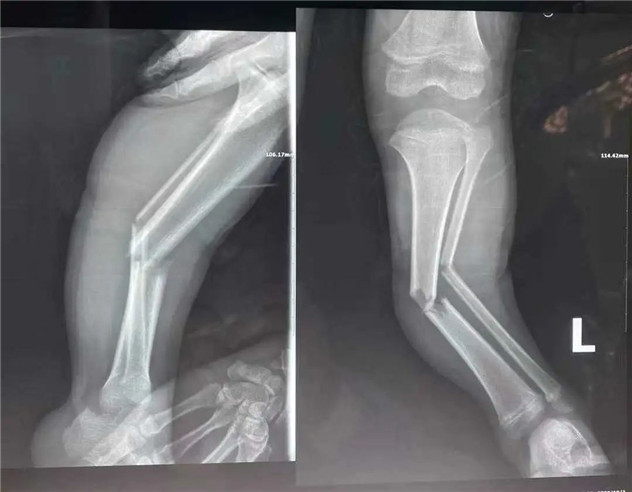

2020年10月3日,家住普陀的睿睿在樓下玩耍時(shí)被來往的電瓶車撞倒在地,左小腿立即腫脹疼痛無法行走。睿睿媽媽見狀馬上撥打120,緊急送他至我院檢查。

經(jīng)拍片顯示,睿睿左脛腓骨中段粉碎性骨折。接診的我院骨科中心主任羅軍建議其入院接受手術(shù)治療。

術(shù)前